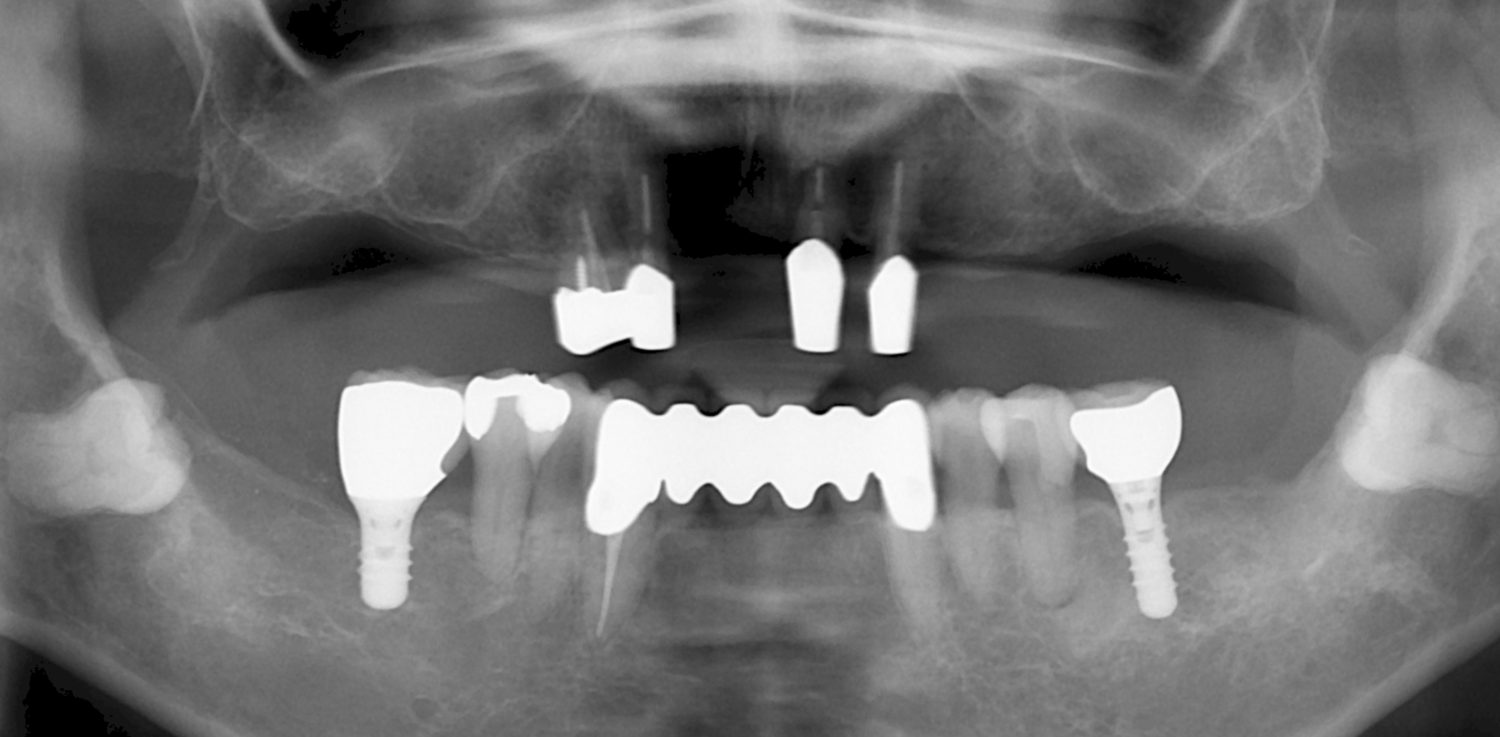

| 主訴 | 60代女性 他院で義歯を作ったが噛みにくい、バネを掛けている左下の銀歯が何度も取れる、しっかり噛めるようになりたい |

| 治療内容 | 歯周病組織再生療法、インプラント治療、セラミック治療を行いました。 |

| 治療費 | 4,000,000円(税込み) |

| 治療期間 | 1年半 |

| 治療回数 | 25回 |

| 想定されたリスク | 失活歯が多く、太くて長い土台がすでに入っていたので、歯根破折のリスクがあった |